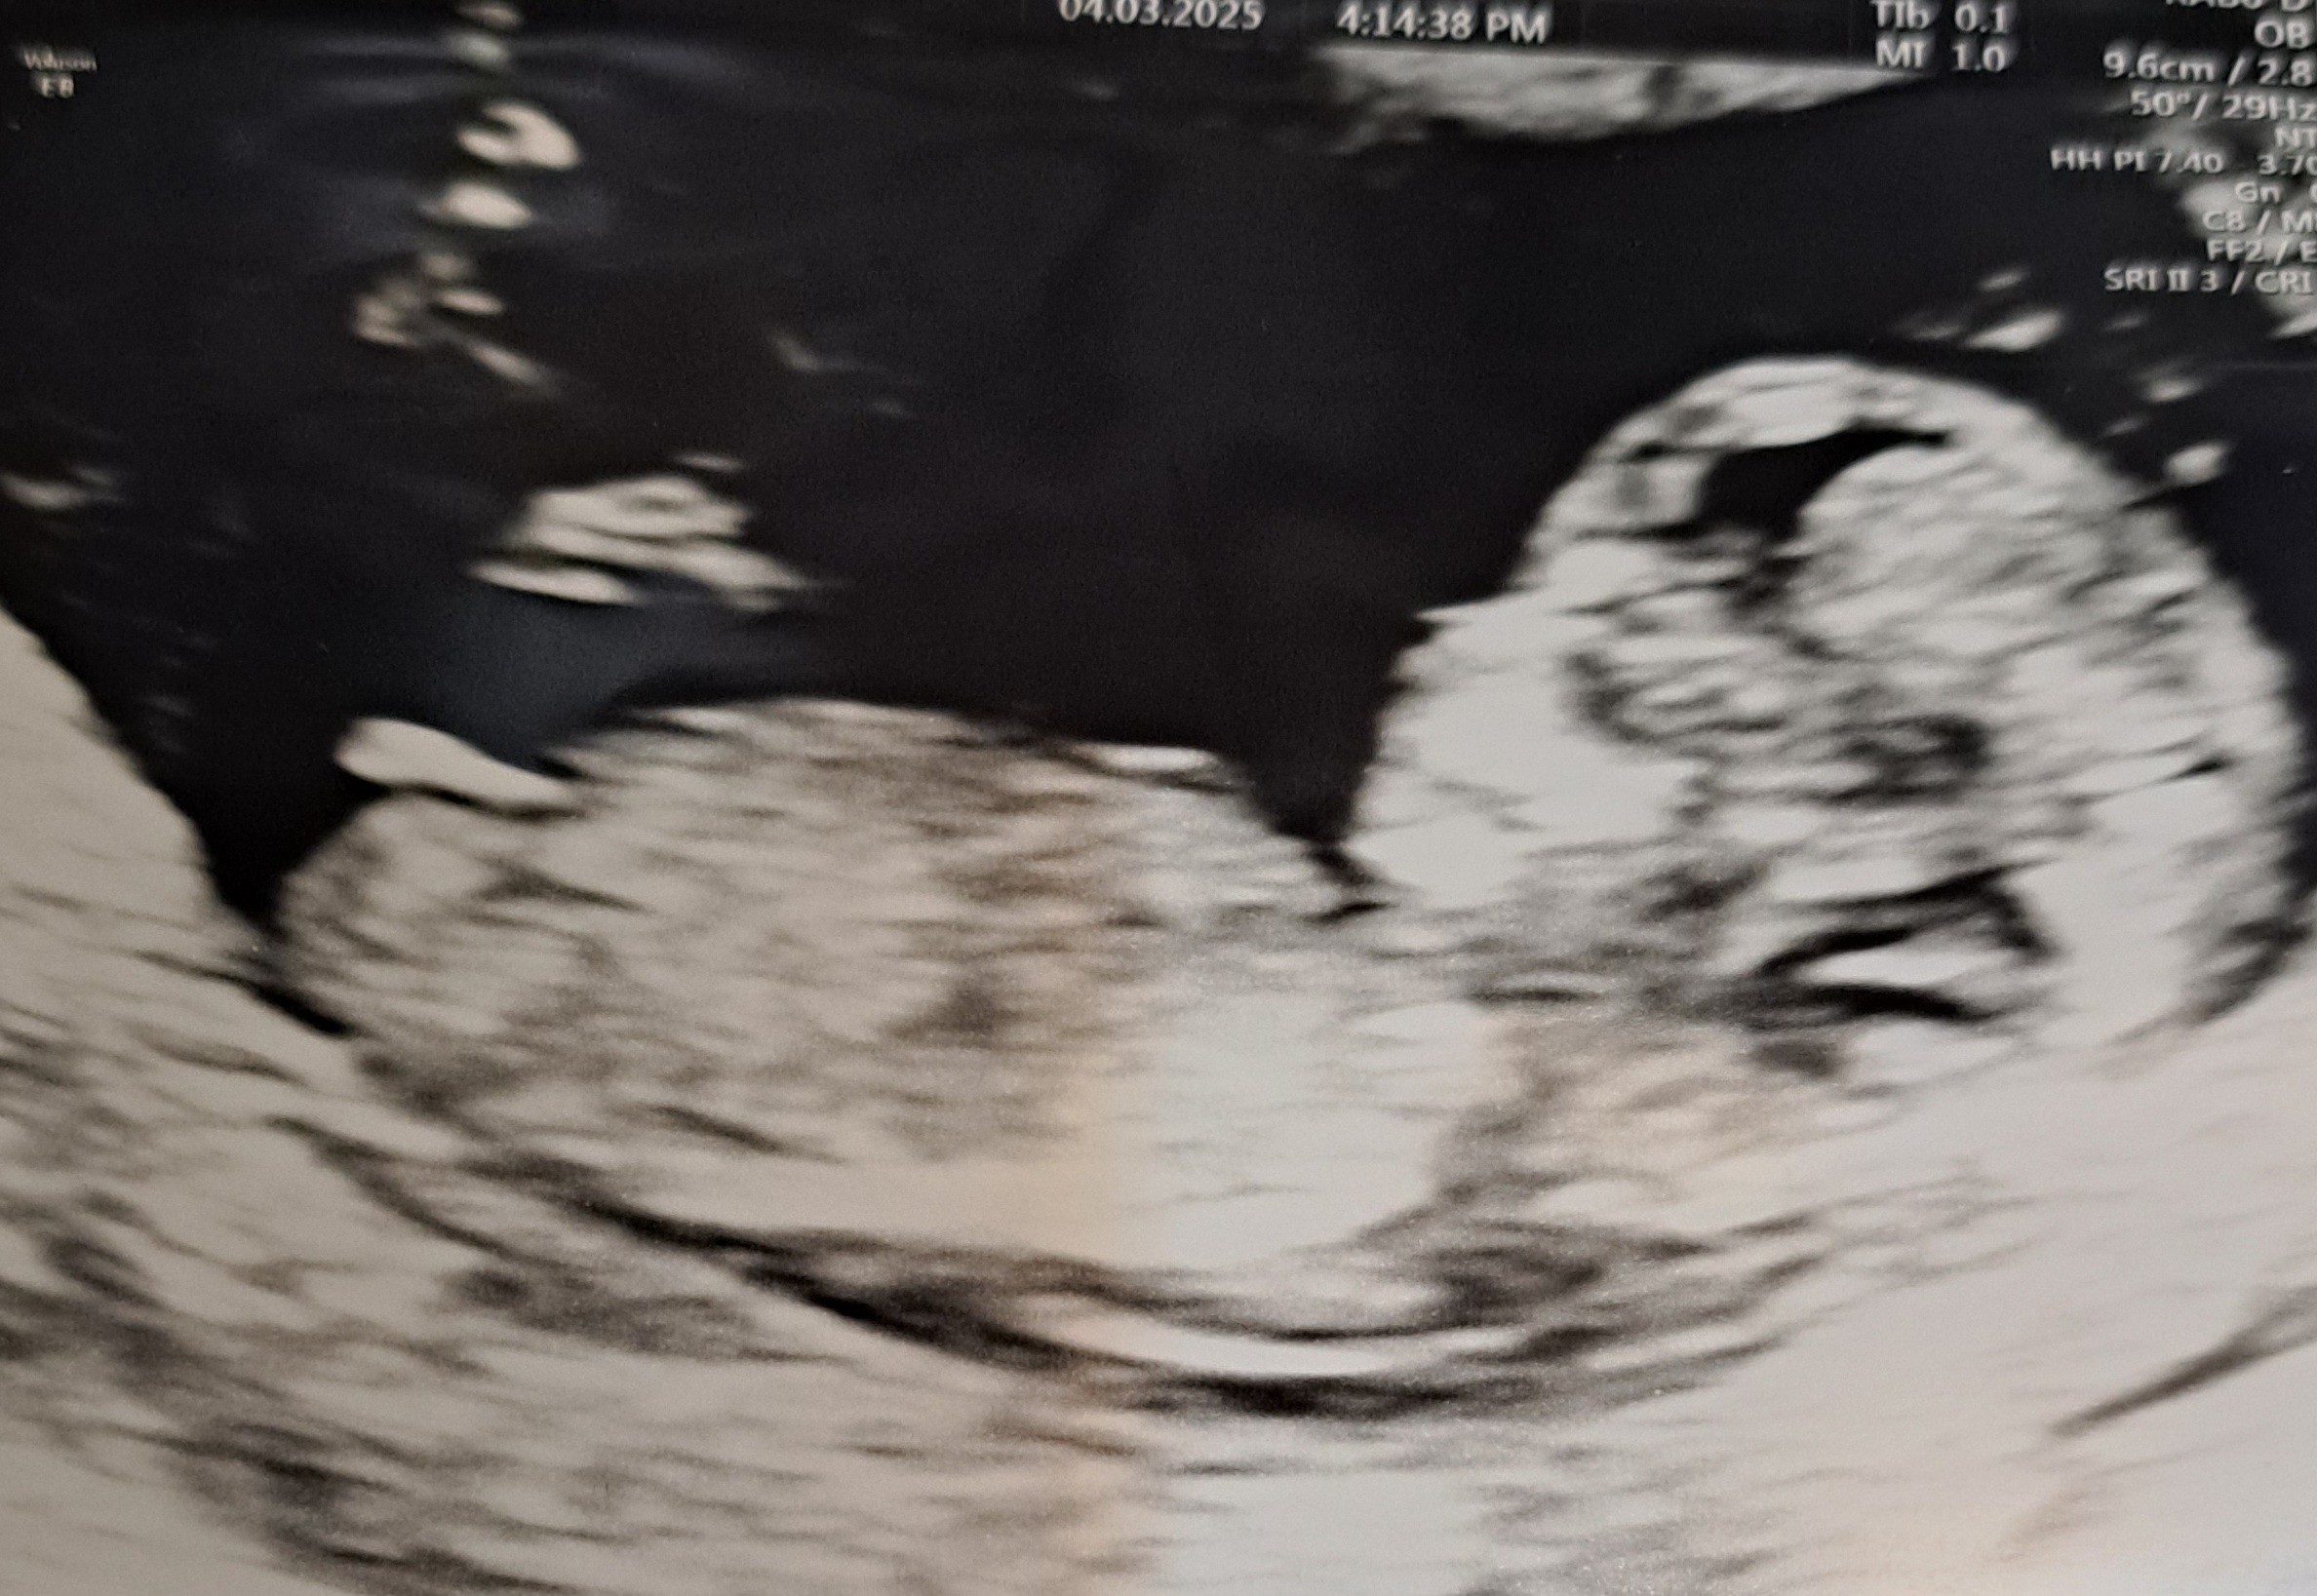

Witam przyszłe mamy, czy któraś z Was potrafi określić płeć dziecka po zdjęciu? Bardzo mi zależy ponieważ przygotwowujemu niespodziankę dla prababci :)

Wydaje mi się, że to chłopiec.

Ale nie biorę za to żadnej odpowiedzialności.

Dziękuję za odpowiedzi. Oczywiście pytałam lekarza ale w dniu badania nie chciał nam powiedzieć może nie był pewien albo się droczyl. Ja powiedziałam że jak mi powie w 12 tygodniu to pewnie jest pewien że chlopak. Na to lekarz że jak stoi to chlopak a jak lerzy dziewczynka po czym zrobił zdjęcie i kazał nam się zastanawiać ;) Na kolejnym usg tak się maluszek kręcił że nie dało się nic uchwycić.